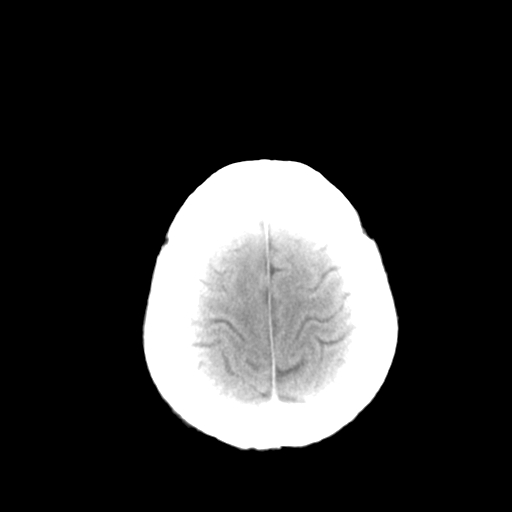

标题: CT13482:对称钙化!外伤就诊! [打印本页]

标题: CT13482:对称钙化!外伤就诊!

女,58 ,对称钙化!外伤就诊!

甲旁减可能.

常见病考虑甲旁低及fahr病等,结合病人体态、实验室检查、家族史等综合考虑。

考虑为:甲状旁腺机能低下或fahr氏病。建议:结合临床及实验室检查。